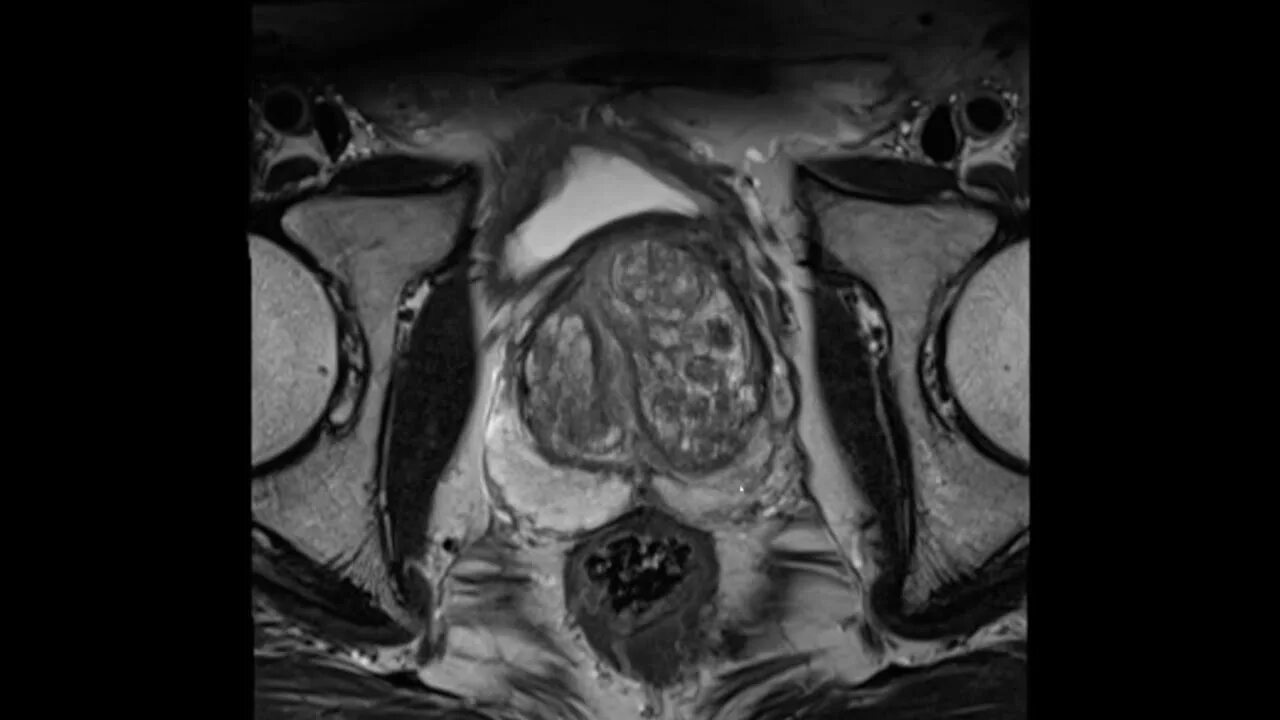

Перед мрт простаты